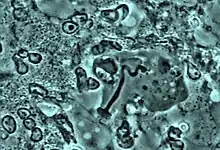

Avancement du processus de phagocytose. Le noyau s'enroule à l'intérieur de l'amibe